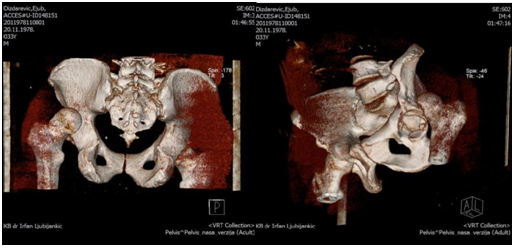

The patient at the age of 34 and 150kg of body weight suffered left hip posterior dislocation with femoral head fracture in car crash accident. The patient had been admitted to hospital after midnight. The mechanism of injury goes as follows: axial force and flexion in the hip caused by impact of the car. The left leg clinically observed is in painful extension, with minimal movement, strong pain and shortened leg. X-rays shows posterior hip joint dislocation and fracture of the femoral head. Closed reduction under anesthesia was unsuccessful. 3D CT reconstruction that had been taken before proceeding to open procedure shows posterior hip dislocation with femoral head fracture above fovea involving weight bearing portion- Pipkin type II fracture dislocation.

Preoperative x-rays, CT scans and 3D CT reconstructions in emergency department are presented as follows (Figure 1-5).

Figure 4 Preoperative 3D reconstructions.

Figure 5  Preoperative 3D reconstructions.